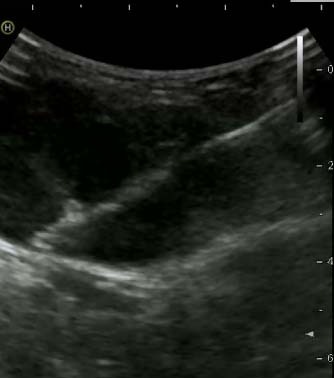

Фото: Трепан-биопсия новообразования под УЗ-навигацией

С целью постановки диагноза опухоли кости рекомендовано применение трепан-биопсии (с помощью специального устройства и биопсийной иглы через прокол кожи и окружающих опухоль тканей производят забор столбиков ткани опухоли) и инцизионной биопсии (через разрез кожи и окружающих тканей удаляется фрагмент опухоли). При выполнении трепан-биопсии применяют различные способы навигации: ультразвук, рентгенография, компьютерная томография.

Фото: Трепан-биопсия новообразования под КТ-навигацией